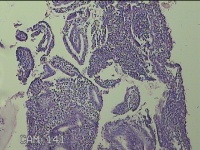

宫腔内容物

性别

女

年龄

53岁

临床诊断

异常子宫出血

一般病史

不规则阴道流血6天。

标本名称

大体所见

灰白暗红色不规则碎组织2x1.8x0.3cm一堆。